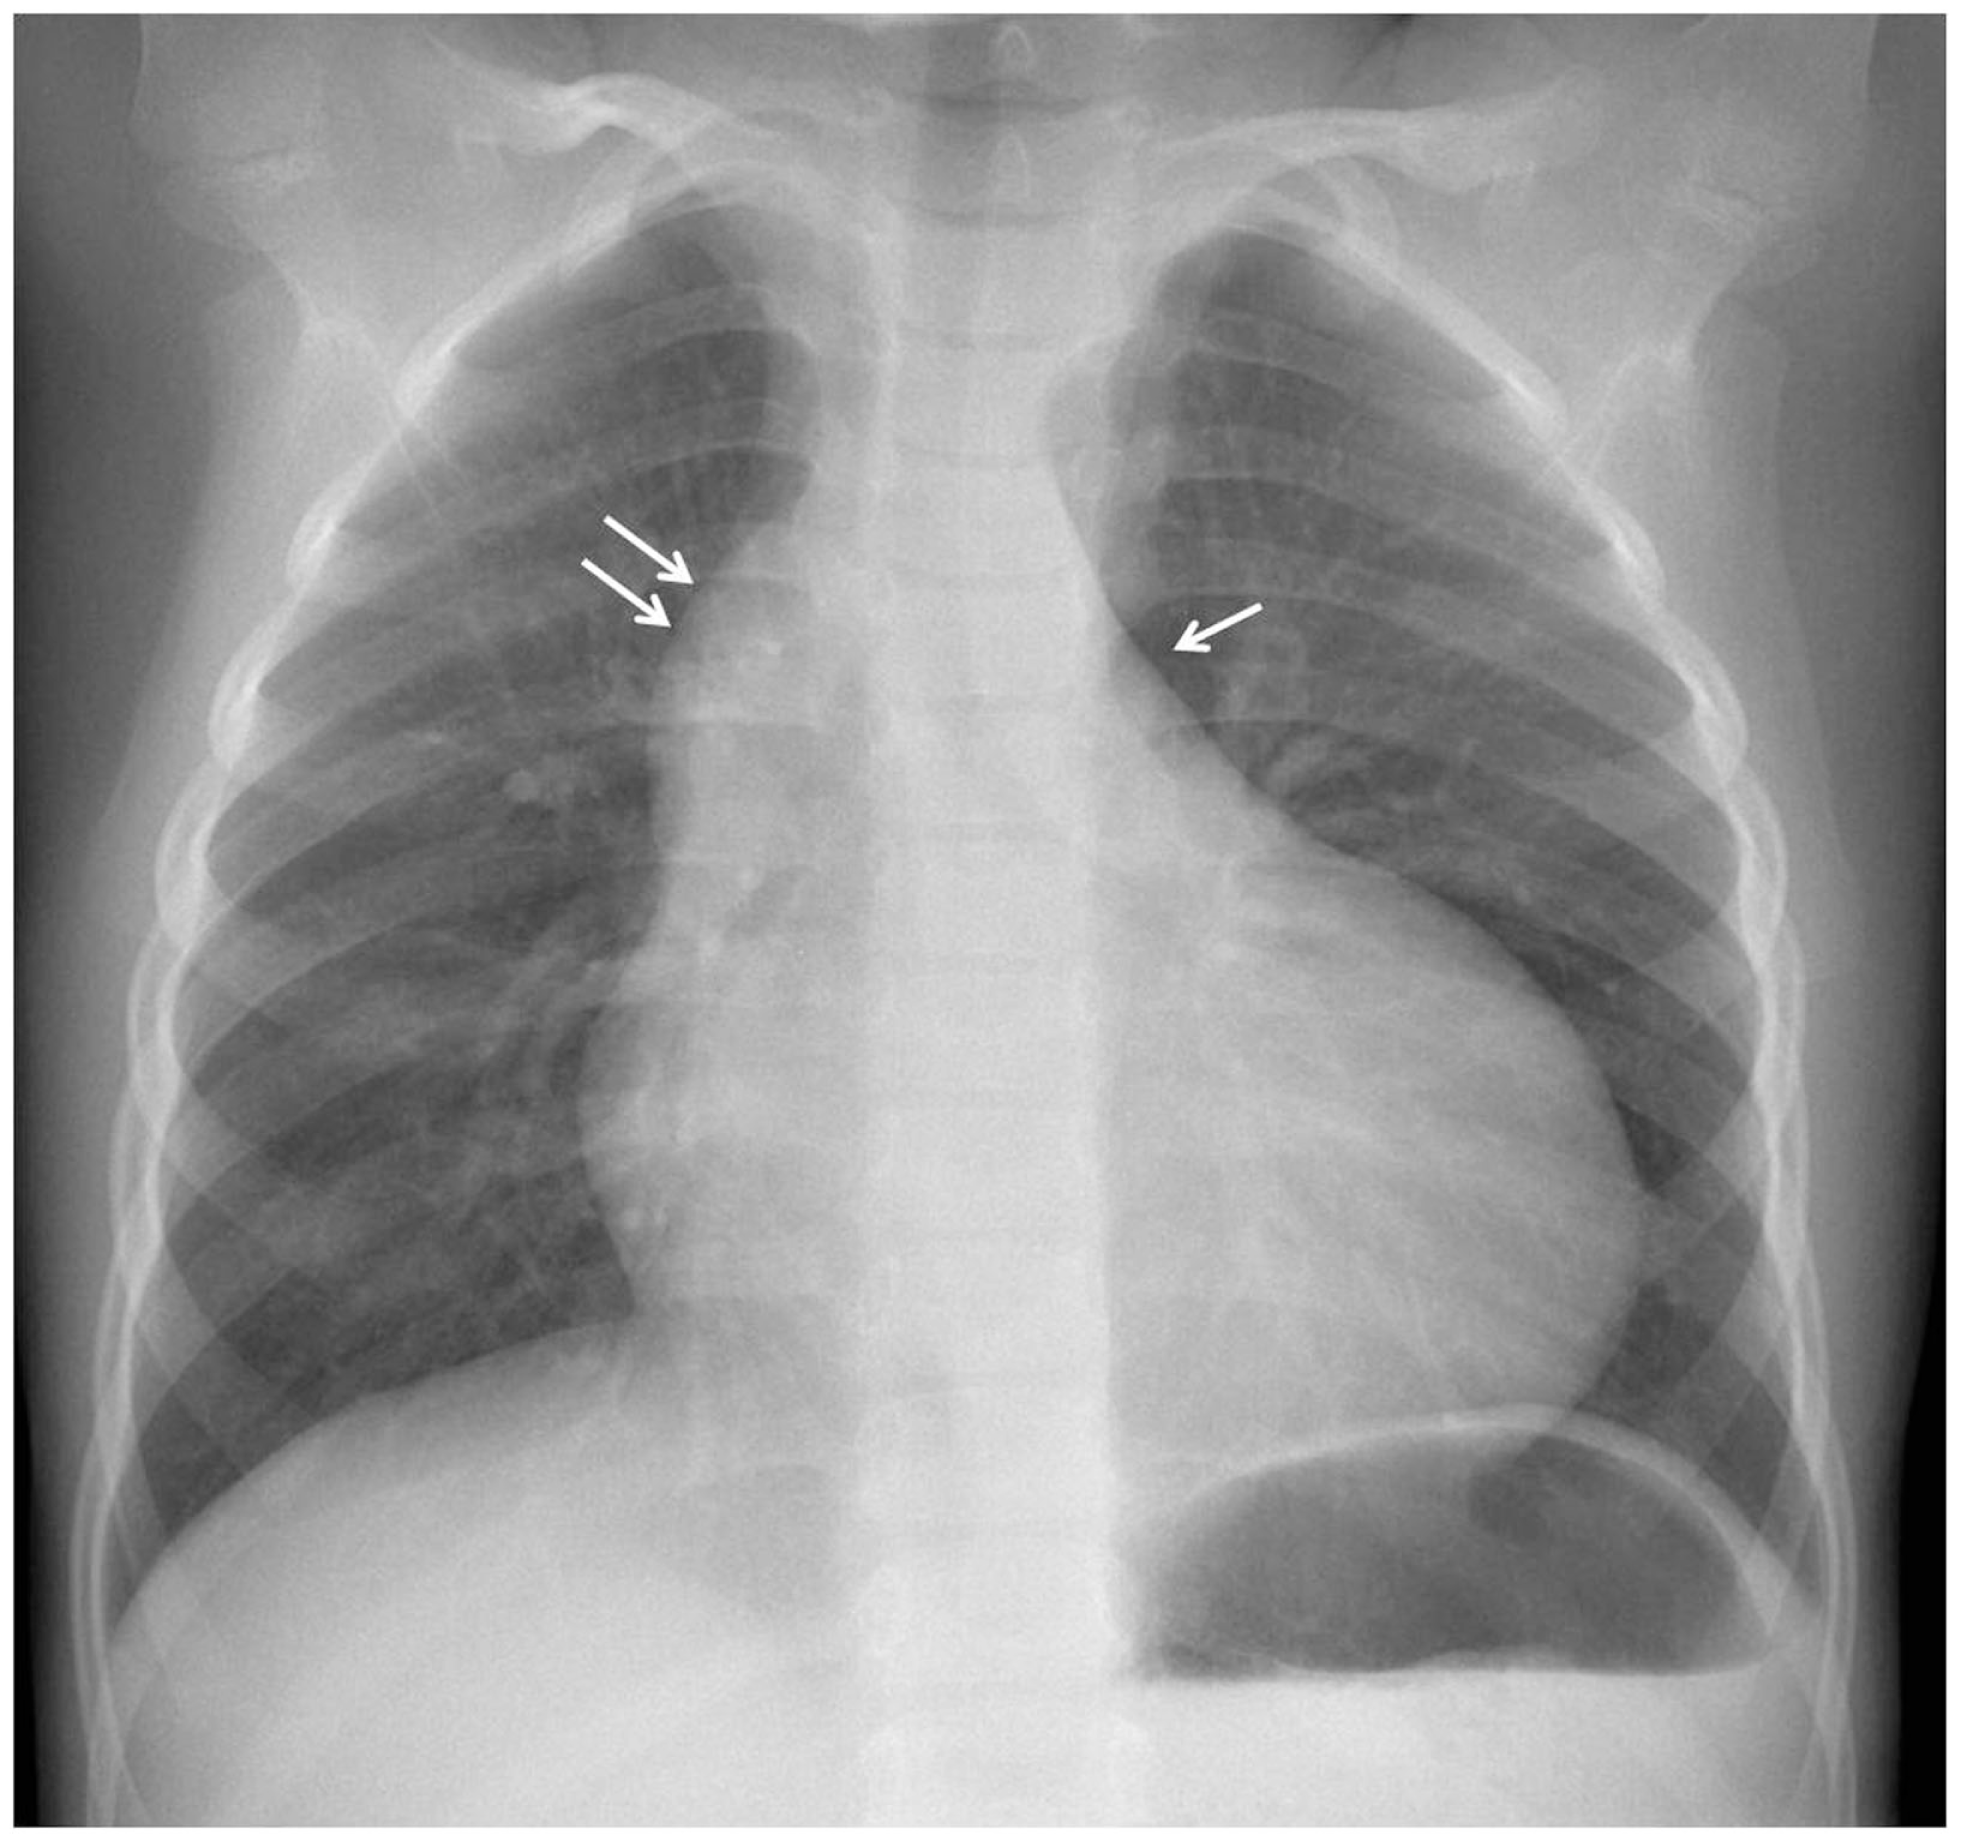

The electrocardiogram showed sinus rhythm with signs of left auricular hypertrophy, but no ventricular hypertrophy. The chest radiography (Figure 1) showed mild cardiomegaly (ICT 0.64) and an absent aortic knob, compatible with the diagnosis of coarctation. The echocardiography showed a bicuspid aortic valve (Figure 2) with severe stenosis (peak systolic gradient of 60 mmHg and mean of 30 mmHg), left ventricular hypertrophy (Z-score +3.3), preserved systolic and diastolic function (mitral E/A ratio 1.6; mitral A deceleration time 0.10 s, E/E′ 22 secondary to increased left heart filling pressure), and tortuous aortic arch with narrowing and acceleration of flow at the aortic isthmus (Figure 3). CMR with angiography showed absence of continuity between the ascending aorta distal to the left subclavian artery (Type 1) and the descending aorta, extending over 5 mm. There was a bend in the arch and diverticulum on either side of the zone of discontinuity, making the diagnosis of atresia rather than interruption of the aortic arch. There was no patent ductus arteriosus (PDA), no associated endofibroelastosis and the descending aorta was fed exclusively by massive systemic collateral circulation (Figures 4–6).

Figure 1

Chest X-ray with prominent right cardiac border secondary to dilatation of the ascending aorta (double arrow) and absent aortic knob (arrow).